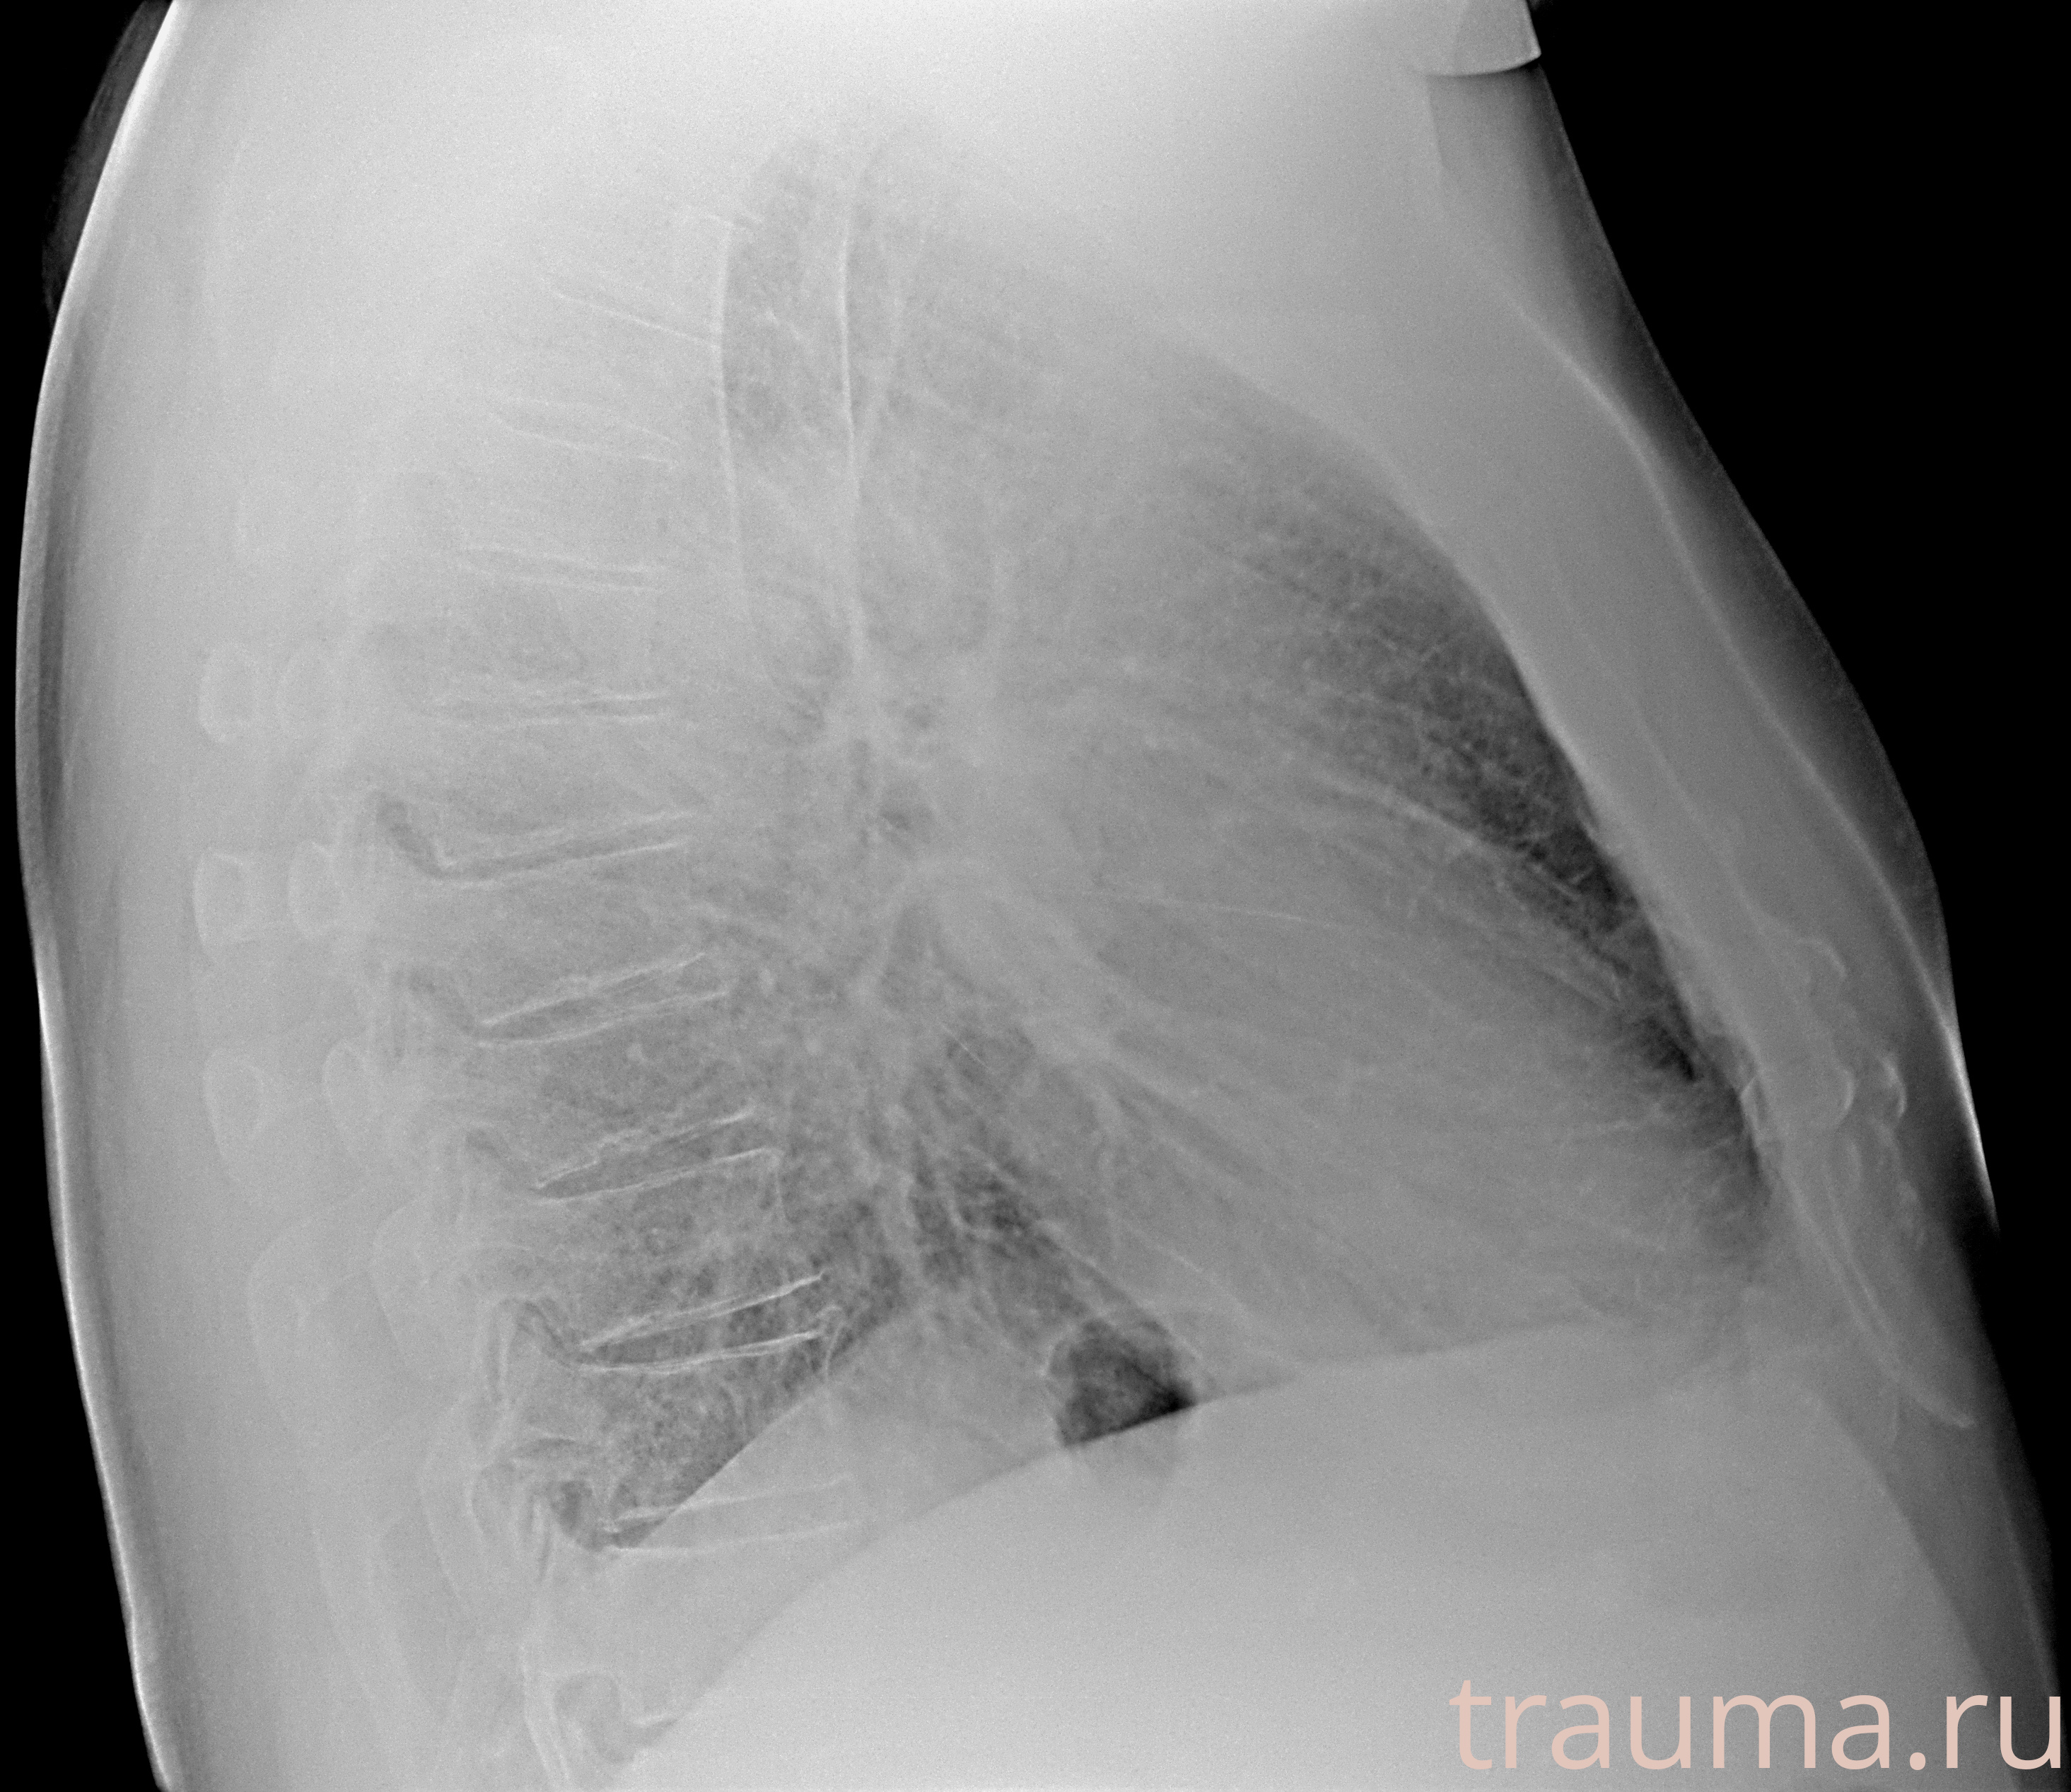

Рентгенограммы

Рентген на дому: по вашему адресу приезжает врач-рентгенолог, травматолог-ортопед с мобильным рентгеновским аппаратом, проводит диагностику травмы или заболевания, делает необходимые рентгенограммы, дает рекомендации по дальнейшему лечению. Получить качественные снимки в домашних условиях возможно благодаря уникальной методике, разработанной МосРентген Центром для института  Склифосовского